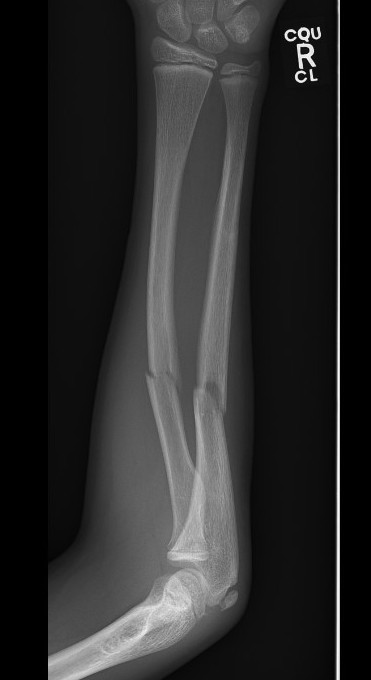

Types

Complete

Greenstick

Buckle / torus

Single or both bone

Galeazzi / Monteggia

Manipulation under anaesthesia

Post reduction Positioning / Rule of Thirds

1. Fracture proximal to the insertion of Pronator Teres

Proximal fragment supinated by biceps

- supinate the forearm

- match proximal fragment

2. Fracture in the middle third

Midposition / neutral

- biceps / pronator teres balanced

3. Fracture in the distal third

Proximal fragment pronated by pronator teres

- pronation is the position of choice